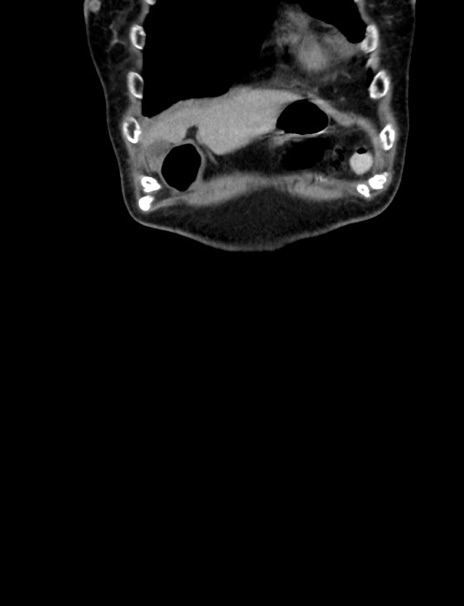

横断像